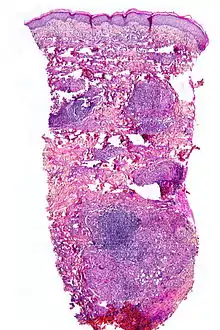

NL is diagnosed by a skin biopsy, demonstrating superficial and deep perivascular and interstitial mixed inflammatory cell infiltrate (including lymphocytes, plasma cells, mononucleated and multinucleated histiocytes, and eosinophils) in the dermis and subcutis, as well as necrotising vasculitis with adjacent necrobiosis and necrosis of adnexal structures. Areas of necrobiosis are often more extensive and less well defined than in granuloma annulare. Presence of lipid in necrobiotic areas may be demonstrated by Sudan stains. Cholesterol clefts, fibrin, and mucin may also be present in areas of necrobiosis. Depending on the severity of the necrobiosis, certain cell types may be more predominant. When a lesion is in its early stages, neutrophils may be present, whereas in later stages of development lymphocytes and histiocytes may be more predominant.